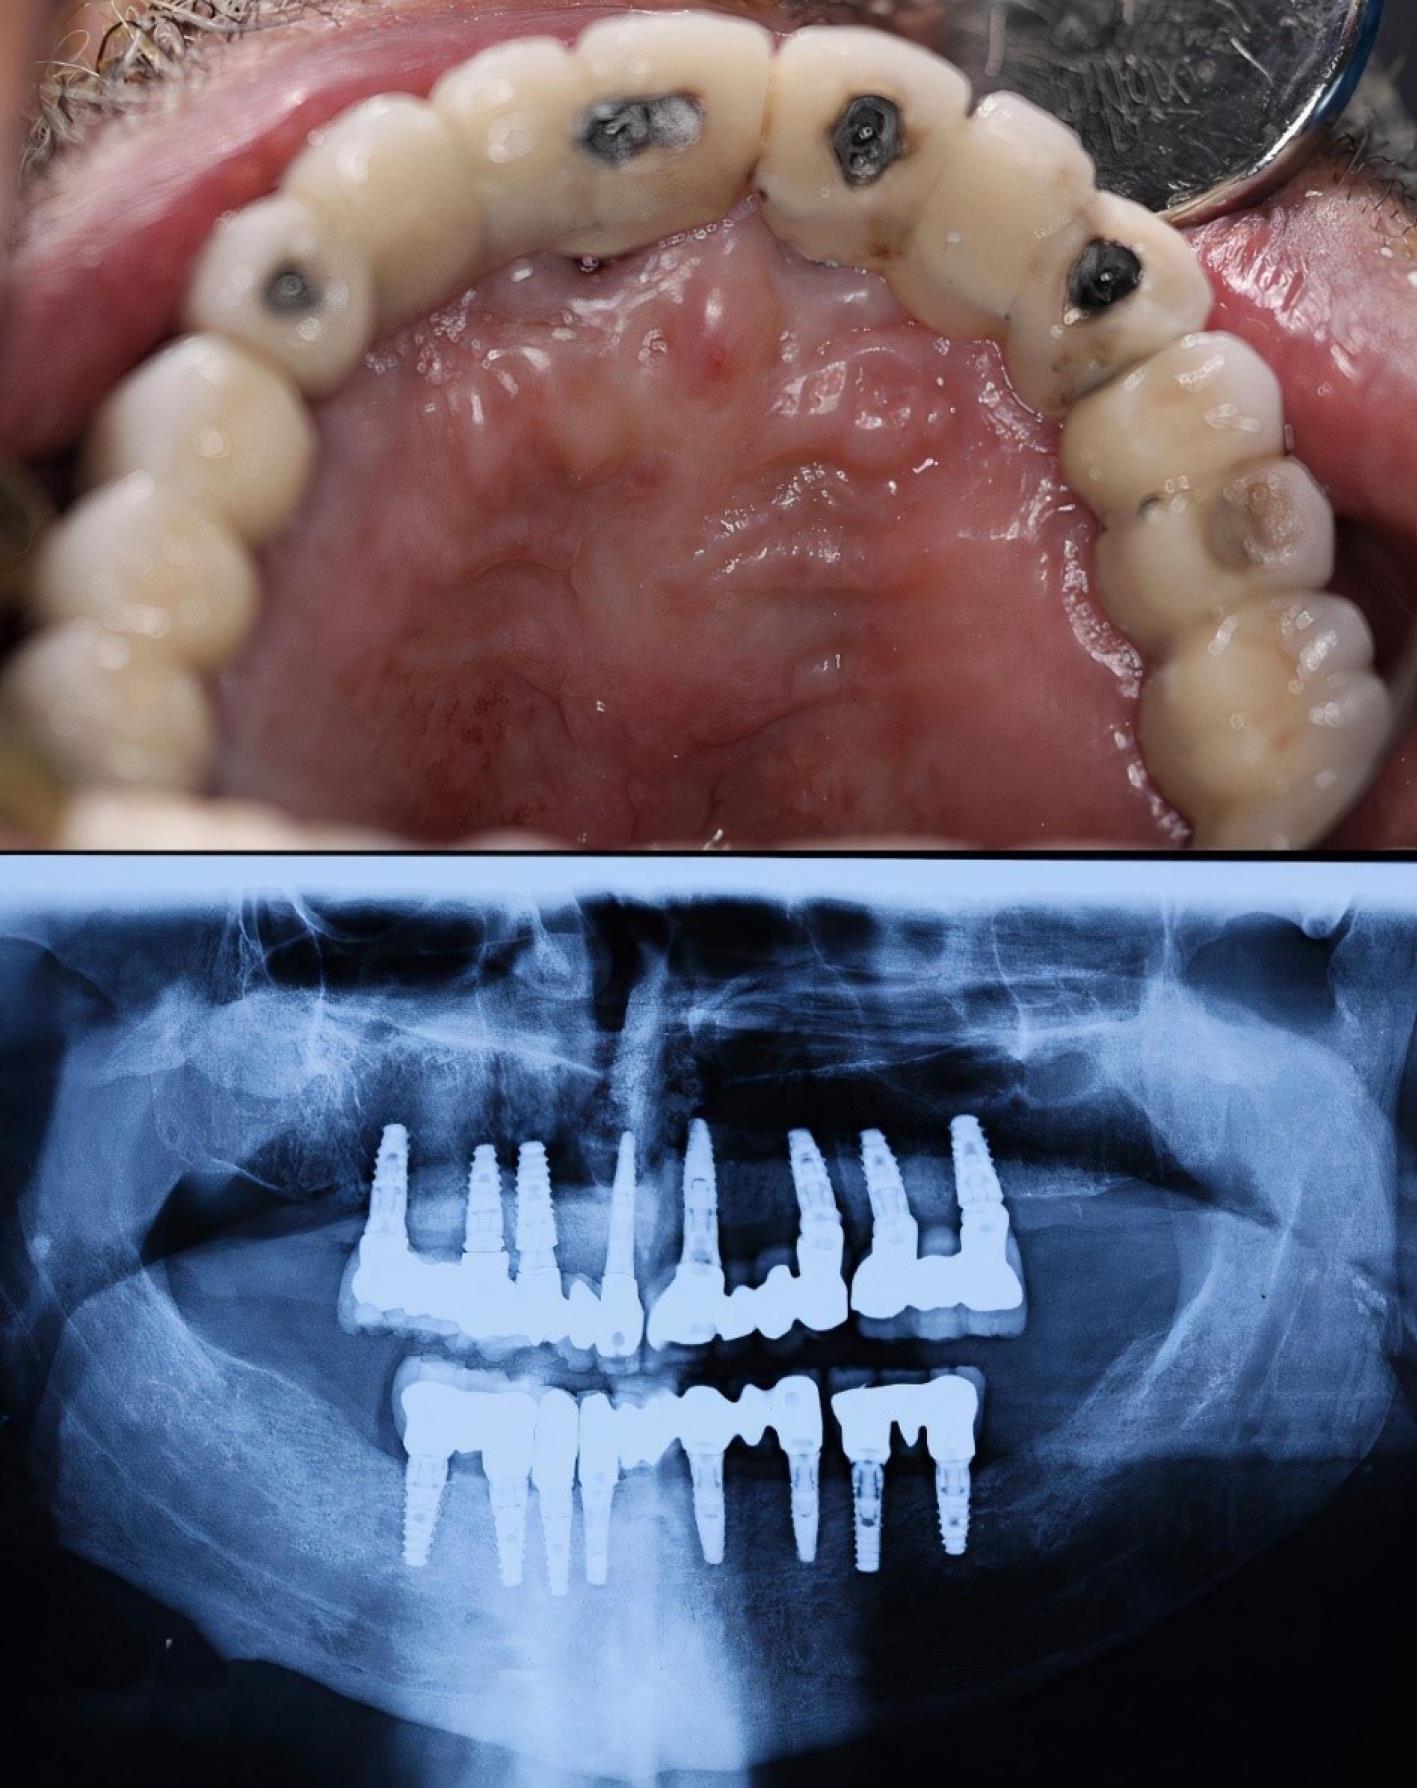

After ten days, the sutures were removed. The patient reported no pain or discomfort during the healing period and was completely satisfied with the treatment outcome. After six months, a panoramic radiograph was retaken. The radiolucency and swelling had completely disappeared. The prosthesis was removed for a reason other than surgical removal of NPDC (porcelain chipping) (Figure 5).

Figure 5.

Postoperative clinical and panoramic views of the maxilla after six months